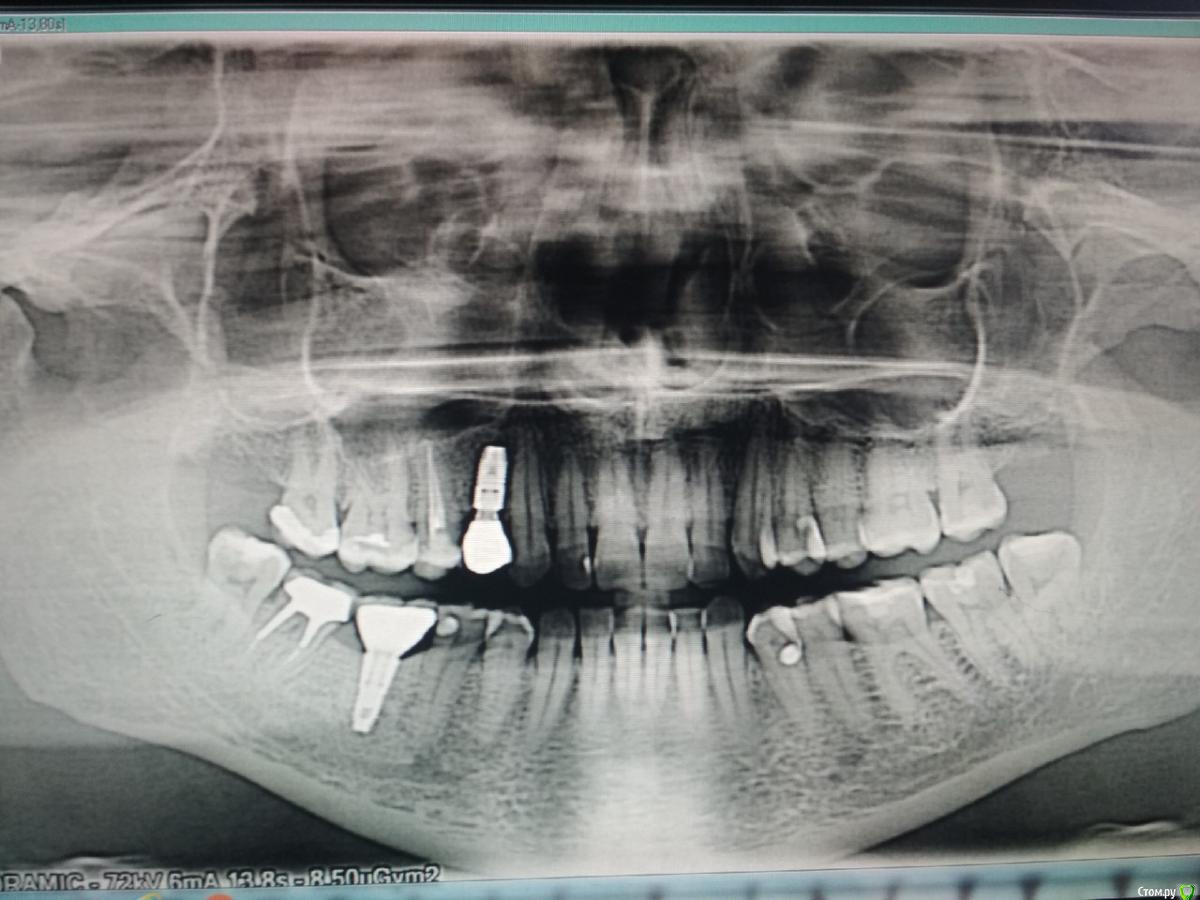

mediis Опубликовано 24 июня, 2019 Поделиться Опубликовано 24 июня, 2019 Здравствуйте! 07.06.2019 мне удалили одновременно два зуба - 7-й и 8-й на нижней челюсти справа с одномоментной имплантацией 7-го. Во время анестезии я почувствовала пронизывающую боль, как электрическим током в районе 2 и 3-го зубов снизу справа, как будто игла задела нерв. После окончания действия анестезии и до настоящего момента отсутствует чувствительность этих 2,3,4-го зубов, онемела правая половина нижней губы и часть подбородка в этой зоне. И еще, появился белый треугольник на лице в районе носогубной части. Нечувствительные зубы ломит, есть ощущение распирания в районе импланта.Посмотрите пожалуйста снимок, вернётся ли чувствительность? Что делать? Врач уверяет, что все отлично, порекомендовал пропить нейромультивит. К сожалению, могу отправить только ссылки на файл. До операции - https://cloud.mail.ru/stock/2UZAKrd1ainvCmjJm9cKMi9Y После - https://cloud.mail.ru/stock/GfEAhknzD8Q61eww4mqRcGc2 Ссылка на комментарий

mediis Опубликовано 24 июня, 2019 Автор Поделиться Опубликовано 24 июня, 2019 (изменено) Вот снимки после удаления 7-го и 8-го и одномоментной имплантантации 7-го и до операции. Изменено 24 июня, 2019 пользователем mediis Ссылка на комментарий

red_butler Опубликовано 25 июня, 2019 Поделиться Опубликовано 25 июня, 2019 я бы убрал имплант в позиции 4.7 2 Ссылка на комментарий

Bier Опубликовано 26 июня, 2019 Поделиться Опубликовано 26 июня, 2019 Да, имплантат нужно убрать Ссылка на комментарий